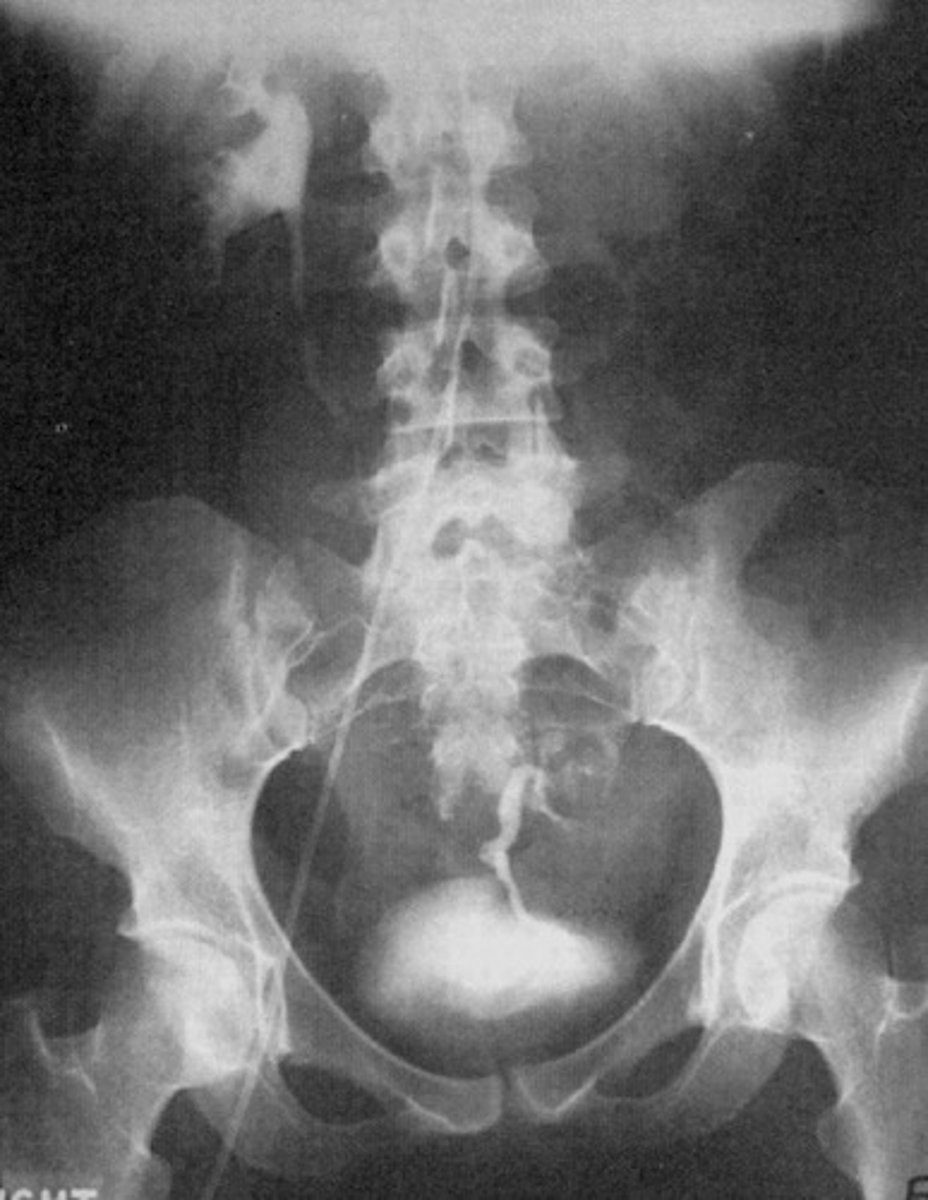

Staghorn Calculus

What is a large stone that completely fills the renal pelvis?

- Renal Calculi (Kidney Stones)

- Calcium

- Uric Acid

- Non-Contrast CT

- IVU

- UVJ and UPJ

- What hard deposits form in the kidneys from minerals and salts in the urine?

- What is 80% of these hard deposits made of that causes them to appear radiopaque on a radiograph?

- What are the other radiolucent hard deposits made of?

- What is the modality of choice for finding these hard deposits?

- What radiographic exam shows points where the ureters are obstructed and filling defects caused by the hard deposits?

- Where do these hard deposits usually obstruct?